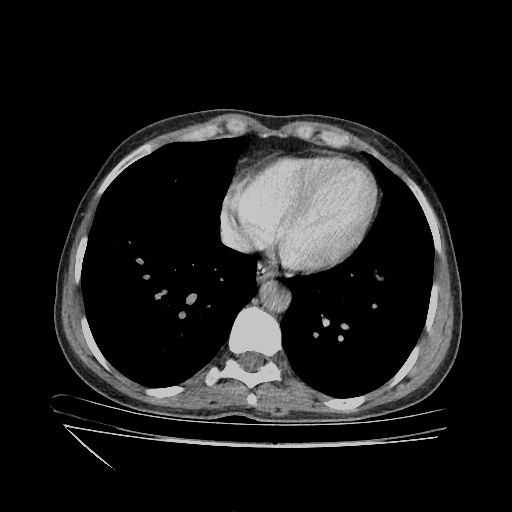

Original VENOUS CT scan

No window - Raw intensity values

Lung window (WL -600, WW 1500 β†’ Low βˆ’1350, High +150)